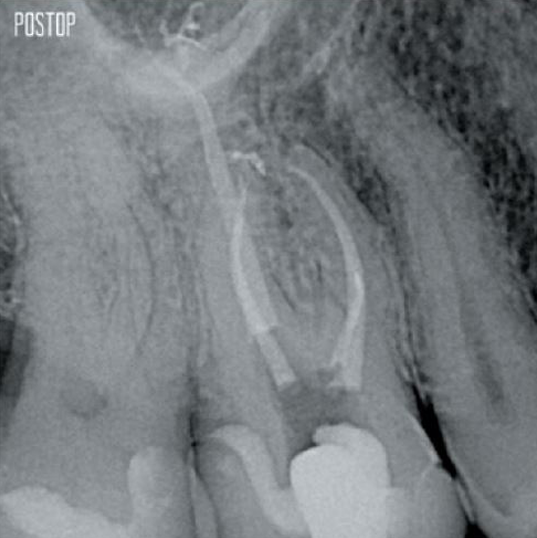

Mehr erhaltenes Dentin. Angemessene Formgebung, Spülung und Obturation gewährleistet.

Fotos mit freundlicher Genehmigung von Dr. Ahmed Salman